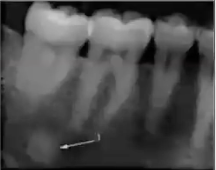

What is this PA showing?

Calcification filling the sinus, widened PDL, spiked appearance of roots seen in osteosarcoma

What is this PA showing?

Osteosarcoma resembling focal cemento-osseous dysplasia